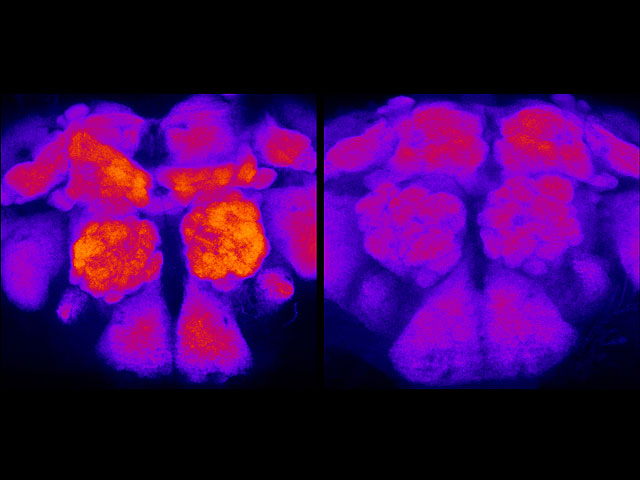

En étudiant des cerveaux de drosophiles – les uns après une période d'intense activité et d'autres après un temps de repos –, des psychiatres de l'université du Wisconsin-Madison (États-Unis) ont démontré le pouvoir purificateur du sommeil. Les protéines sécrétées par les cellules neuronales au cours des différentes activités (en rouge, à gauche) sont largement éliminées après le repos (à droite). Lorsque la mouche s'est beaucoup fatiguée, les protéines sont très concentrées dans les zones du cerveau associées à l'apprentissage. Après un « p’tit som », le taux de protéines baisse, indiquant que les synapses redeviennent plus petits.

Source : Science, 3 avril 2009